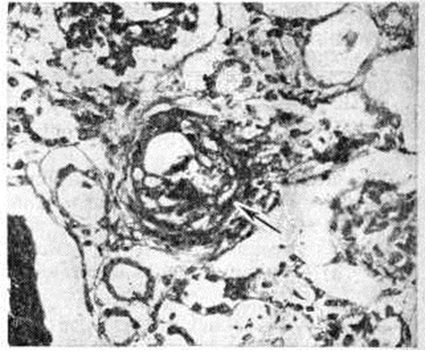

Микроскопически во всех органах обнаруживают характерное поражение капилляров, артериол и мелких артерий, которое наиболее выражено в почках и зависит от длительности течения заболевания. При кратковременном течении (до 1 месяца) и обострении процесса преобладают фибриноидное набухание с плазматическим пропитыванием (рисунок 1) с последующим фибриноидным некрозом сосудов и окклюзией просвета эозинофильными PAS-положительными массами, дающими положительную реакцию на фибрин.